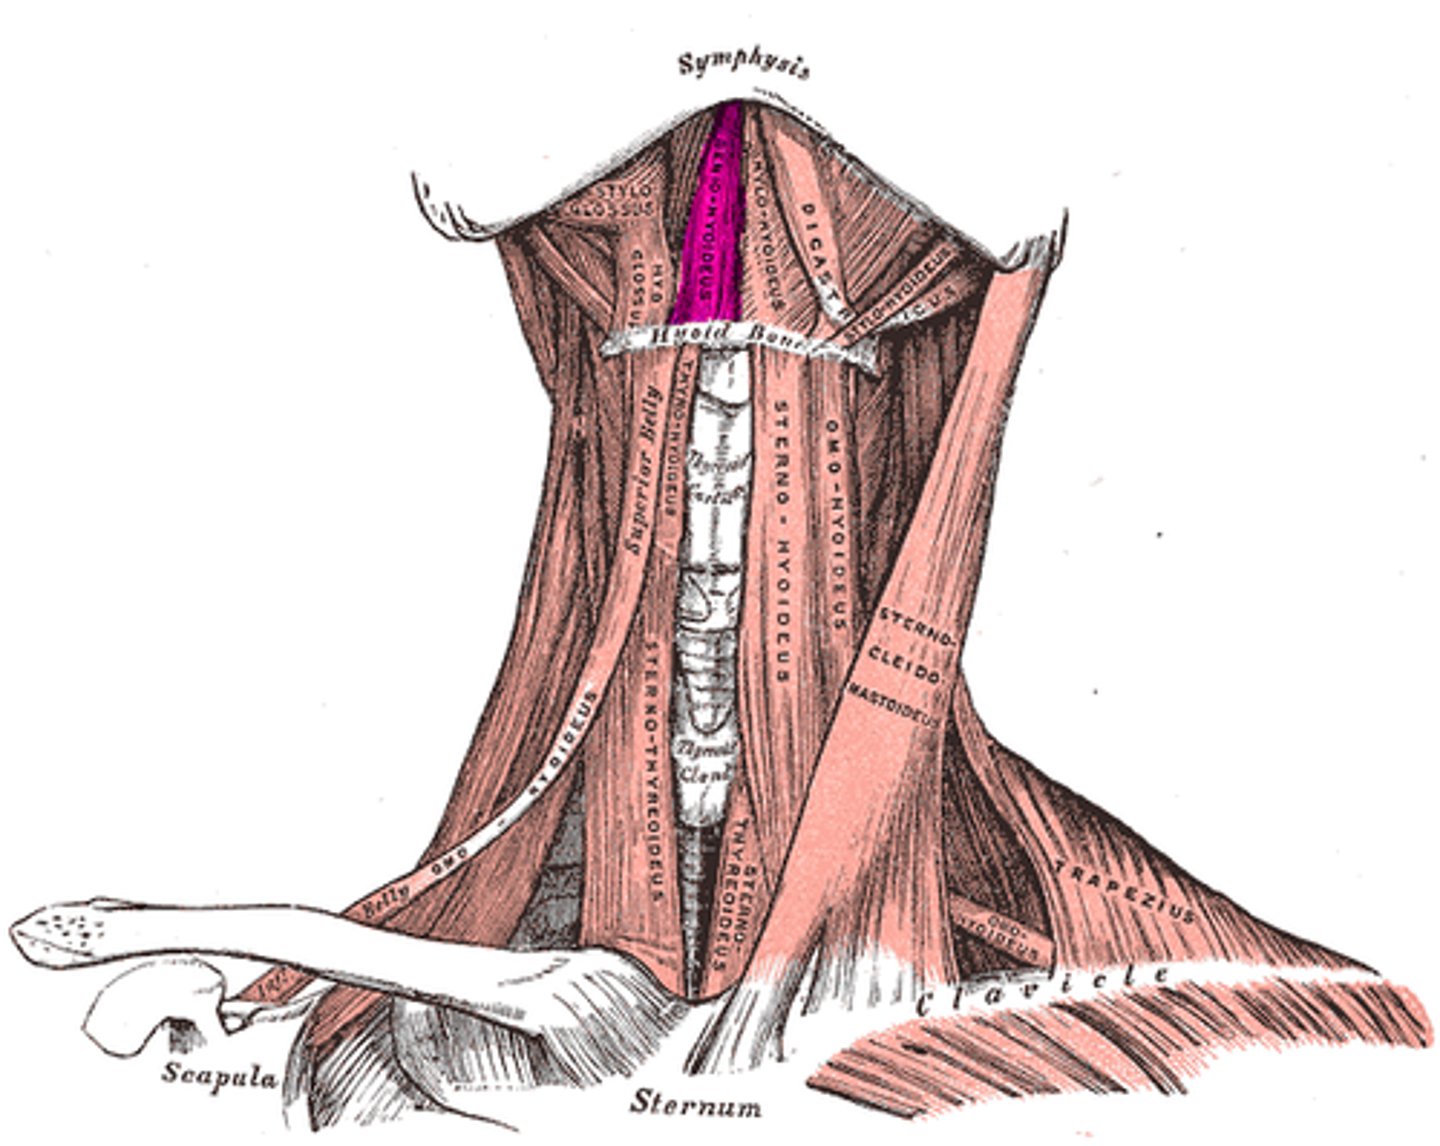

Stylohyoid m.

Origin: Styloid process

Insertion: Hyoid

Action: Elevate, retract

Digastric (two bellies)

Origin: Temporal/Mandible

Insertion: Hyoid

Action: Elevate

Mylohyoid m.

Origin: Mandible

Insertion: Hyoid

Action: Elevate

Geniohyoid m.

Origin: Mandible

Insertion: Hyoid

Action: Protract

Sternohyoid m.

Origin: Clavicle/sternum

Insertion: Hyoid

Action: Depress

Omohyoid (two bellies) m.

Origin: Clavicle/scapula

Insertion: Hyoid

Action: Depress

Thyrohyoid m.

Origin: Thyroid cartilage

Insertion: Hyoid

Action: Depress, Elevate larynx

Sternothyroid m.

Origin: Sternum

Insertion: Thyroid Cartilage Action: Depress

Hyoglossus m.

Origin: Hyoid

Insertion: Tongue (Lateral) Action: Depress, Pull inferior

Genioglossus m.

Origin: Mandible

Insertion: Tongue (Inferior) Action: Protrude, Pull inferior

Styloglossus m.

Origin: Styloid process

Insertion: Tongue

Action: Pull superior

Sternocleidomastoid m.

Origin: Sternum/Clavicle

Insertion: Mastoid Process

Action: Flex, Rotate